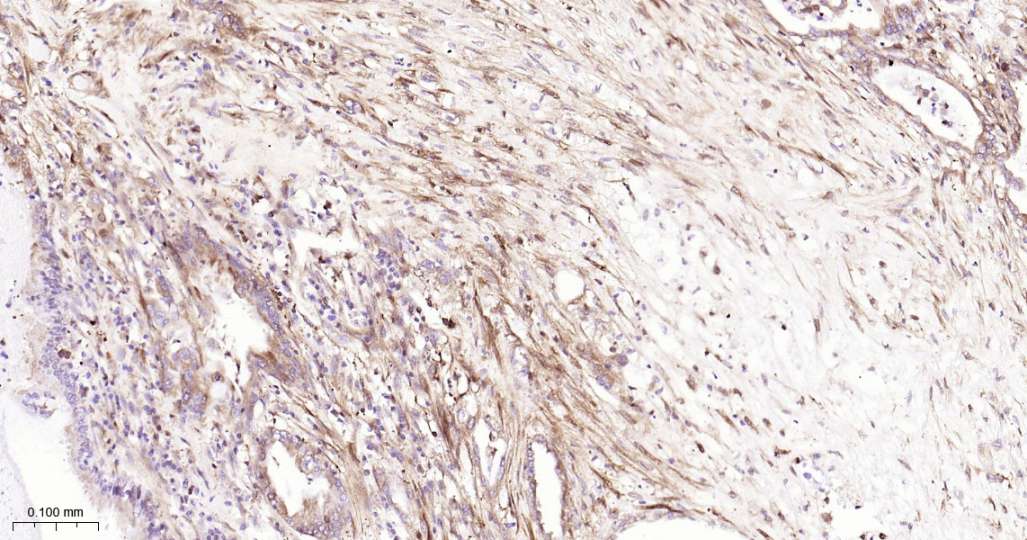

Immunohistochemical analysis of paraffin embedded Human pancreatic cancer tissue slide using IHC0590H (Human PGAM1 Kit).

Immunohistochemical analysis of paraffin embedded Human colon cancer tissue slide using IHC0590H (Human PGAM1 Kit).